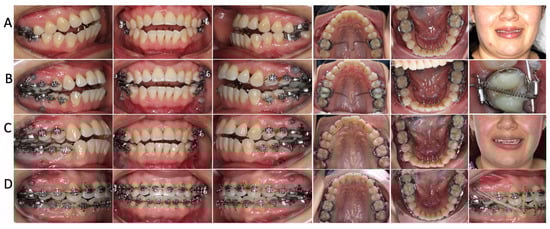

2.4. Treatment Progress